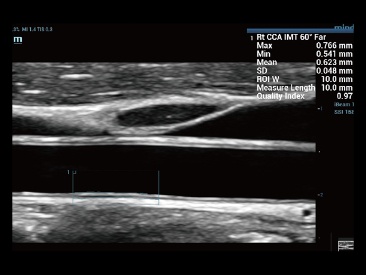

Assim como o n├Łvel de qualidade de imagem premium, o Resona 7 tamb├®m melhora as capacidades de investiga??o cl├Łnica com o revolucion├Īrio Fluxo V para avalia??o hemodin?mica vascular e a aquisi??o de plano mais inteligente do conjunto de dados 3D para diagn├│stico CNS fetal. Combinando a opera??o mais intuitiva baseada em gesto de multi-toques e todos os recursos cl├Łnicos essenciais, Resona 7 est├Ī realmente conduzindo novas ondas na inova??o de ultra-som.